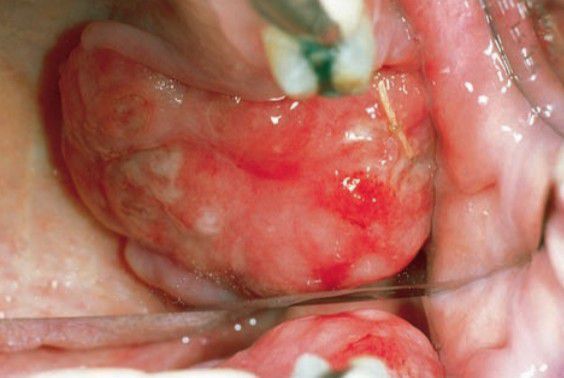

The posterior portions of the jaw are more commonly affected because the marrow spaces are larger. The formation of amyloid from the aggregation of immunoglobulin light-chain proteins is a common sequela of multiple myeloma and when deposited in the tongue can produce macroglossia